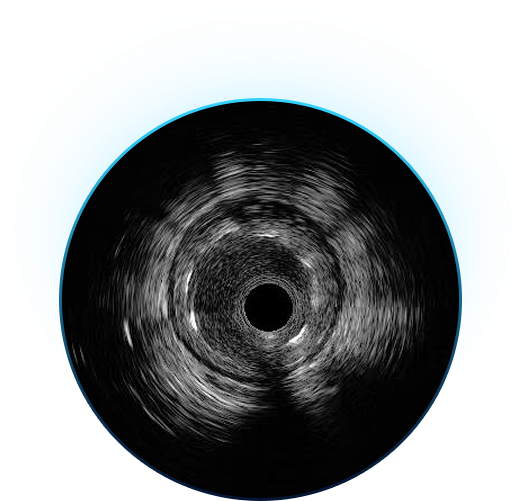

IVUS通过导管技术将微型超声探头送入血管腔内,再通过高密度螺旋扫描,可以清晰获得整个血管内腔和管壁的横断面图像,从而直观地帮助心血管介入医生全面准确地诊断血管狭窄病变的结构和性质,指导介入治疗过程的精准实施,并对治疗结果进行更为充分的评估。IVUS与血流储备分数(FFR)一起,构成了指导实现当代冠心病临床介入(PCI)精准化治疗的影像学和生理学工具。

北芯IVUS产品由VIVOHEART®主机和TRUEVISION®系列导管两部分组成,拥有行业最高的成像分辨率(60MHz超声成像频率)、全球最快的成像速度(100帧/秒断面成像;10mm/s回撤速度),以及inSmartVision高性能图像分析平台和优秀的导管操控性能,能够快速、高效地提供血管腔内全貌图像和丰富的病变信息,指导冠脉精准介入治疗的实施。

1、高清

北芯TRUEVISION®系列导管,采用全自主研发超声换能器;60MHz中心频率为临床用户带来的高清图像,能呈现更多微小结构与病变细节;同时支持40MHz中心频率,提供更多选择满足不同的临床应用需求。